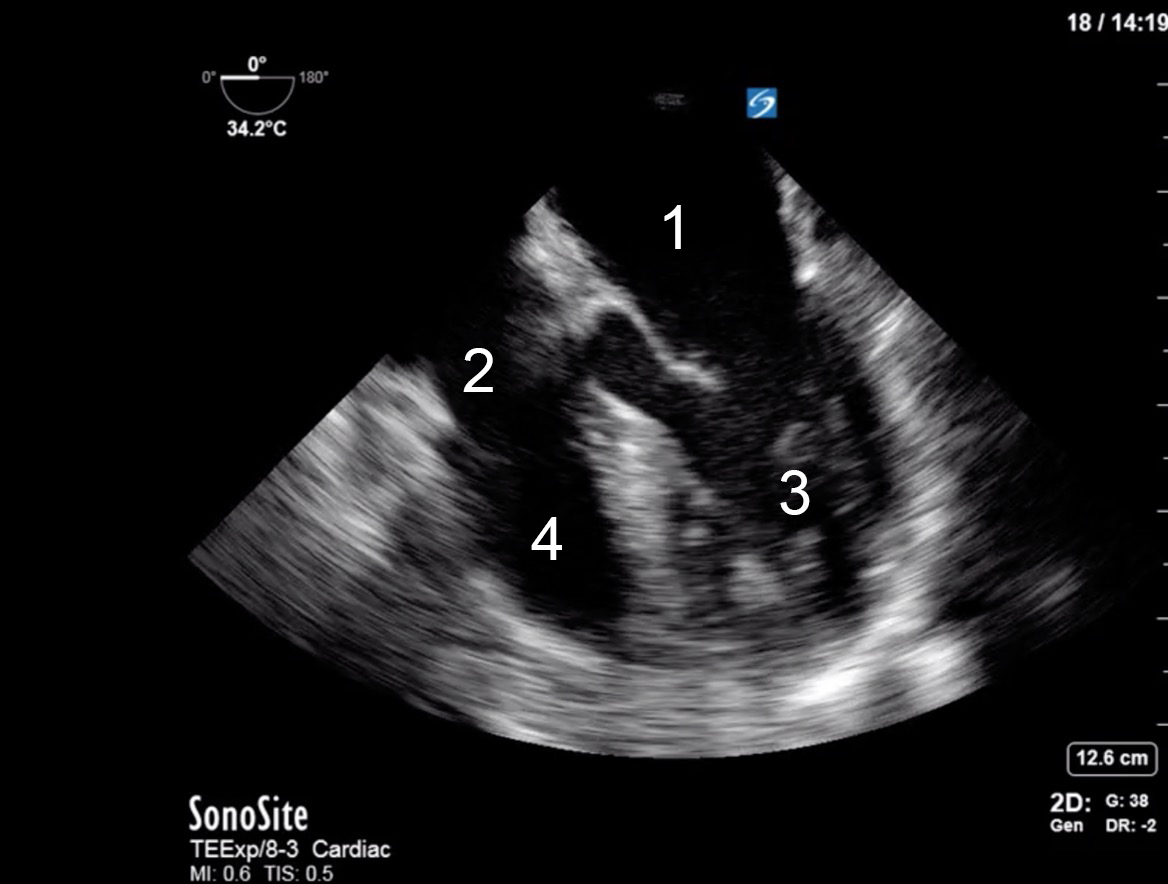

TEE Resus Mid-esophageal 4 Chamber Image

Left Atrium

Right Atrium

Left Ventricle

Right Ventricle